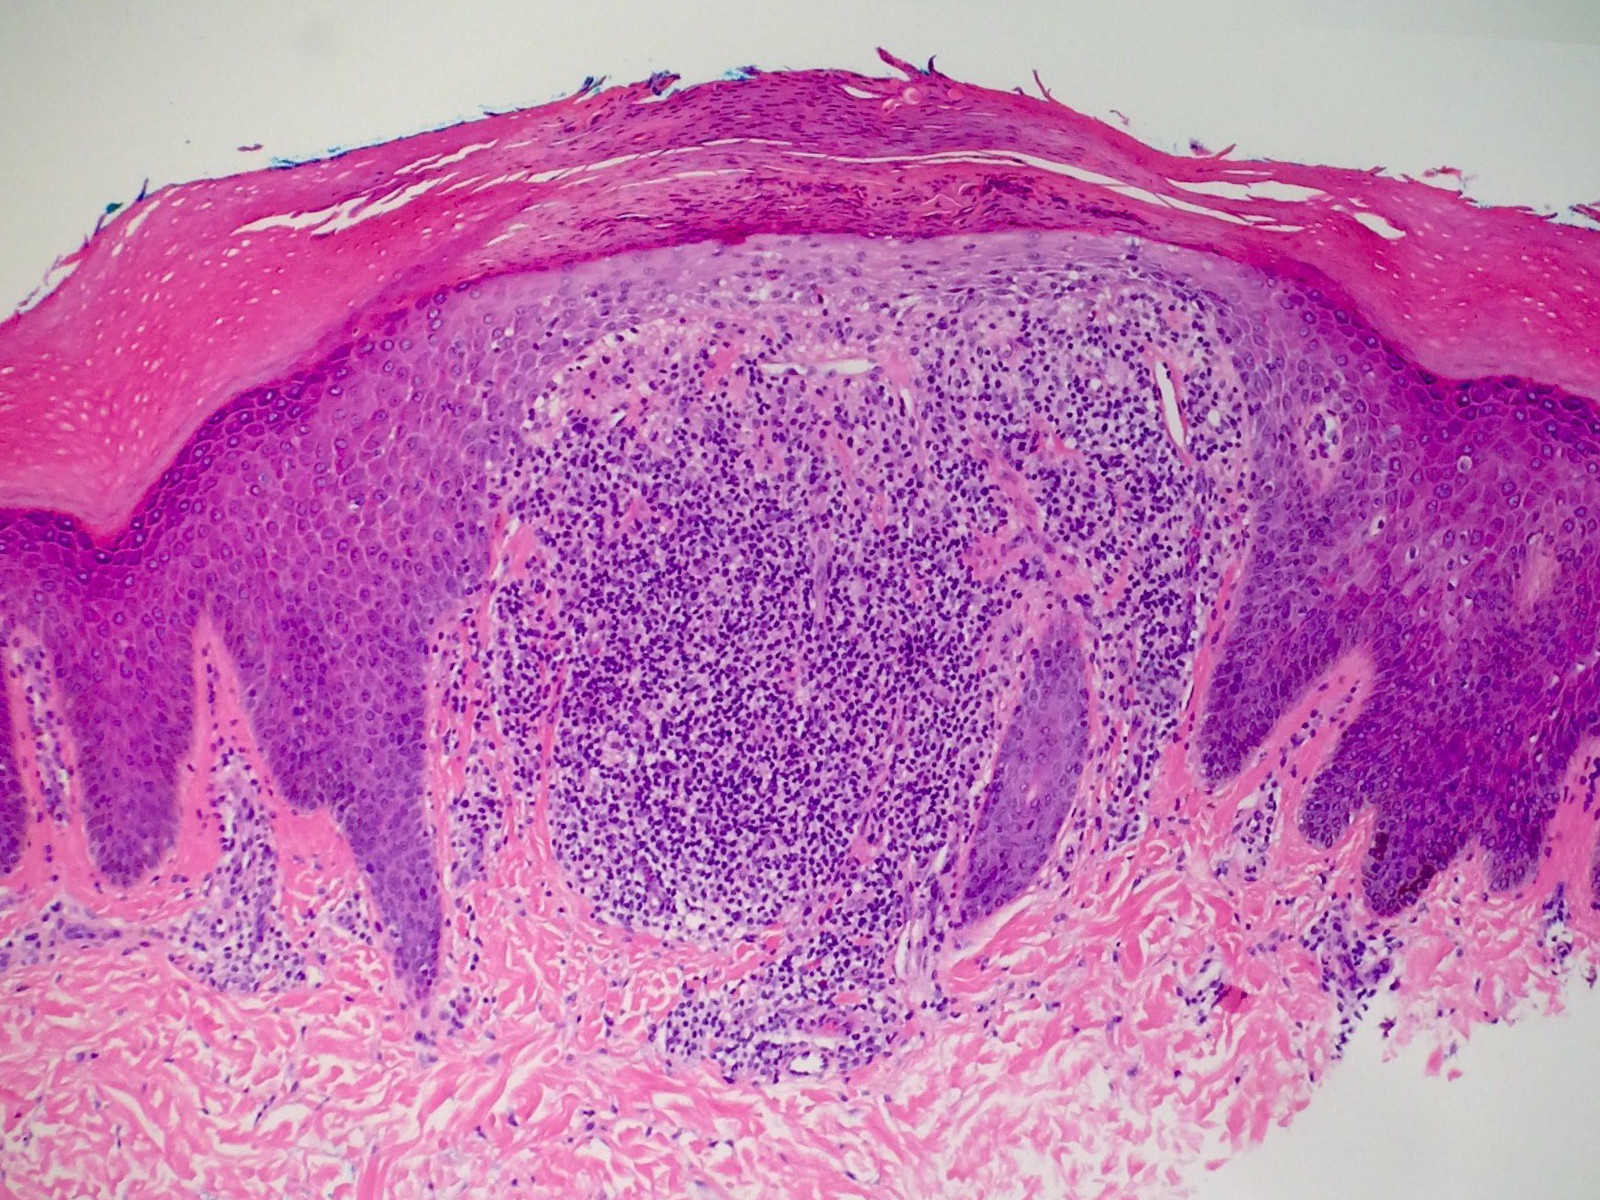

PA:Histologisch is er een granulomateus

lymfohistiocytair ontstekingsinfiltraat dat in een uitgezette dermale papil

ligt. De overliggende epidermis is dun, en de retelijsten aan de zijkanten van

het infiltraat reiken diep waardoor het er uit ziet als een klauw die een bal

vasthoudt (ball-and-claw). Het infiltraat is nodulair en bestaat uit lymfocyten

en (deels epitheloide) histiocyten, gewoonlijk met enkele reuscellen van het

Langhans type. Er zijn enige vacuolaire veranderingen in het grensvlak. Er is

pigmentincontinentie. De epidermis toont hierboven geringe compacte hyperkeratose,

soms parakeratose. Het infiltraat wordt omsloten door verlengde retelijsten

die het infiltraat als het waren 'omarmen' (hugging).